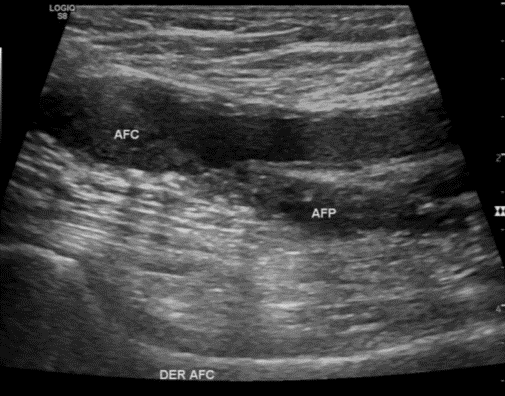

Desgarro Músculos gastrocnemios como hallazgo incidental en ecografía Doppler venoso EEII Der.

Ecotomografía Doppler Venoso